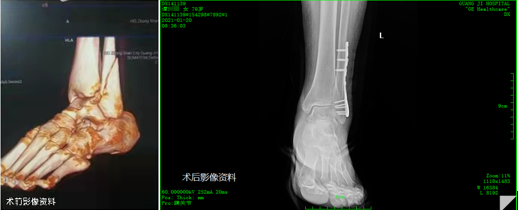

病例二:患者为79岁女性,因外物撞伤倒地致行走困难1小时由急诊入院,经查体、DR摄片检查后诊断为:左外踝、后踝骨折;左足第1楔骨撕脱性骨折。入院后完善检查,经医院骨科组织讨论,在椎管麻醉下行左外踝骨折切开复位内固定术。

1613706387682322.png

陈仲教授仔细查看此患者石膏固定、周围皮肤组织色泽血运、功能位置后,表示关节内固定要求解剖复位,内固定稳定,早期活动大力关节,此手术指征明确、手术及时,术后一定加强主动功能锻炼及协助被动功能锻炼。

杨述华教授对于此次查房的三个患者病例给出了专业的指导意见:病例一患者的手术复位效果良好,胫骨平台骨折治疗不当容易引起创伤性关节炎,一定要及时指导患者功能锻炼;病例二患者手术选择时机及时有效,术式合理,需要加强石膏托固定塑性;病例三患者颈5椎体血管瘤的情况需要密切观察、每半年进行一次MRI复查,必要时行PVP手术。